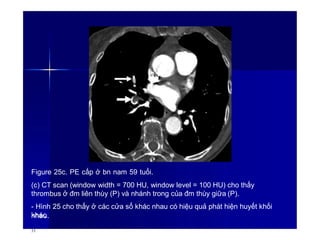

Figure 25c. PE cấp ở bn nam 59 tuổi.

(c) CT scan (window width = 700 HU, window level = 100 HU) cho thấy

thrombus ở đm liên thùy (P) và nhánh trong của đm thùy giữa (P).

- Hình 25 cho thấy ở các cửa sổ khác nhau có hiệu quả phát hiện huyết khối

khác

nhau.